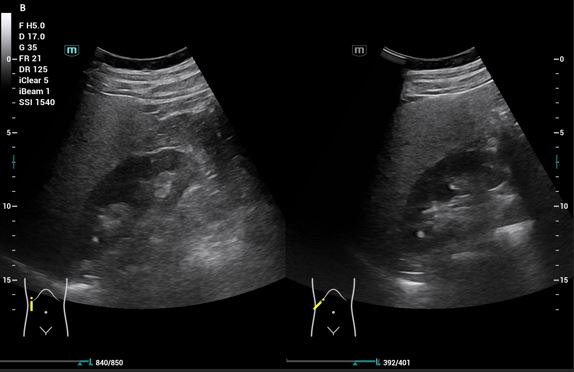

Pruebas complementarias: Sistemático de orina: microhematuria y ecografía abdominal: Riñones: (RD 11 cm, RI 12,09 cm), ecogenicidad, contornos y localización normales. RD: dilatación de la vía excretora Grado I dudosas imágenes de litiasis sin sombra acústica. No se evidencia líquido libre intrabdominal. Vejiga bien replecionada, jet ureteral bilateral simétrico, en trayecto del uréter derecho con Doppler color se observa artefacto de centelleo o efecto twinkling, que sugiere cálculo enclavado en unión vesicoureteral derecha.